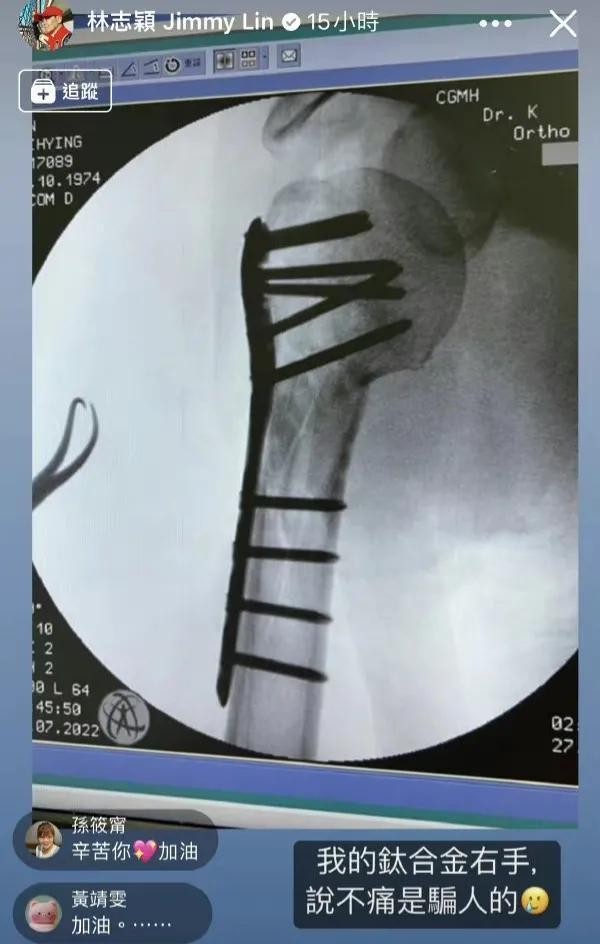

而在另外一则动态中,林志颖首次公开了车祸手术后的“钛合金手臂”的X光片,并配文:“我的钛合金右手,说不痛是骗人的”!

从照片中,我们清晰可见地看到,林志颖的右手采用了钛合金支架以及10根钉子来固定,不难看出,当时受伤还是蛮严重的, 看到他钛合金手臂的X光片,真的是触目惊心,让人心有余悸!